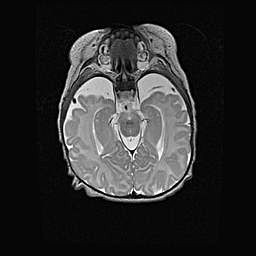

Наружная гидроцефалия с возможной атрофией височных областей.

Возраст: 28 дней

Вес: 3670 г

Пол: мужской

Окружность головы: 38 см

Срок гестации: 40 недель

Гидроцефалия головного мозга у новорожденных – это заболевание, которое характеризуется скоплением избыточного количества спинномозговой жидкости в желудочковой системе головного мозга в результате затруднения её перемещения от места выработки к месту поглощения в кровеносную систему или вследствие нарушения абсорбции. При открытой наружной форме гидроцефалии у новорожденных расширяются и переполняются субарахноидные пространства.

При нормотензивных  формах,  которые,  как  правило,  являются  следствием  перенесенных ишемических  повреждений  паренхимы  мозга,  возможно  сочетание микроцефалии  с нормотензивной гидроцефалией. В основе данных изменений лежит атрофия больших полушарий с преимущественной  локализацией  в  лобно-височных  областях.